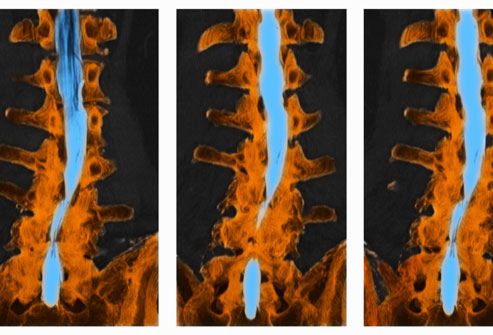

O seu médico pode solicitar exames de imagem, como uma ressonância magnética, para obter mais informações sobre a localização e a causa do nervo irritado. Uma ressonância magnética pode mostrar o alinhamento dos discos, ligamentos e músculos vertebrais. Uma tomografia computadorizada com contraste também pode fornecer uma imagem útil da medula espinhal e dos nervos. Determinar a causa da ciática pode ajudar a orientar o curso do tratamento. Os raios X podem ajudar a identificar anormalidades ósseas, mas não conseguem detectar problemas nos nervos.

O nervo ciático se estende da região lombar até a parte de trás das duas pernas e até os pés. É composto de cinco raízes nervosas (L4, L5, S1, S2 e S3) que se ramificam da coluna lombar. Quando uma das raízes nervosas é comprimida ou irritada, pode levar a sintomas de dor e possivelmente dormência e formigamento que começam na região lombar e irradiam pela nádega e pelas pernas. Esses sintomas são chamados de ciática. As seguintes condições geralmente causam ciática.